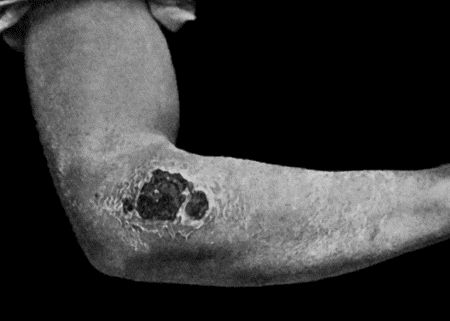

28.Malignant Pustule third day after infection 122

29.Malignant Pustule fourteen days after infection 122

101.Paraffin Epithelioma 394